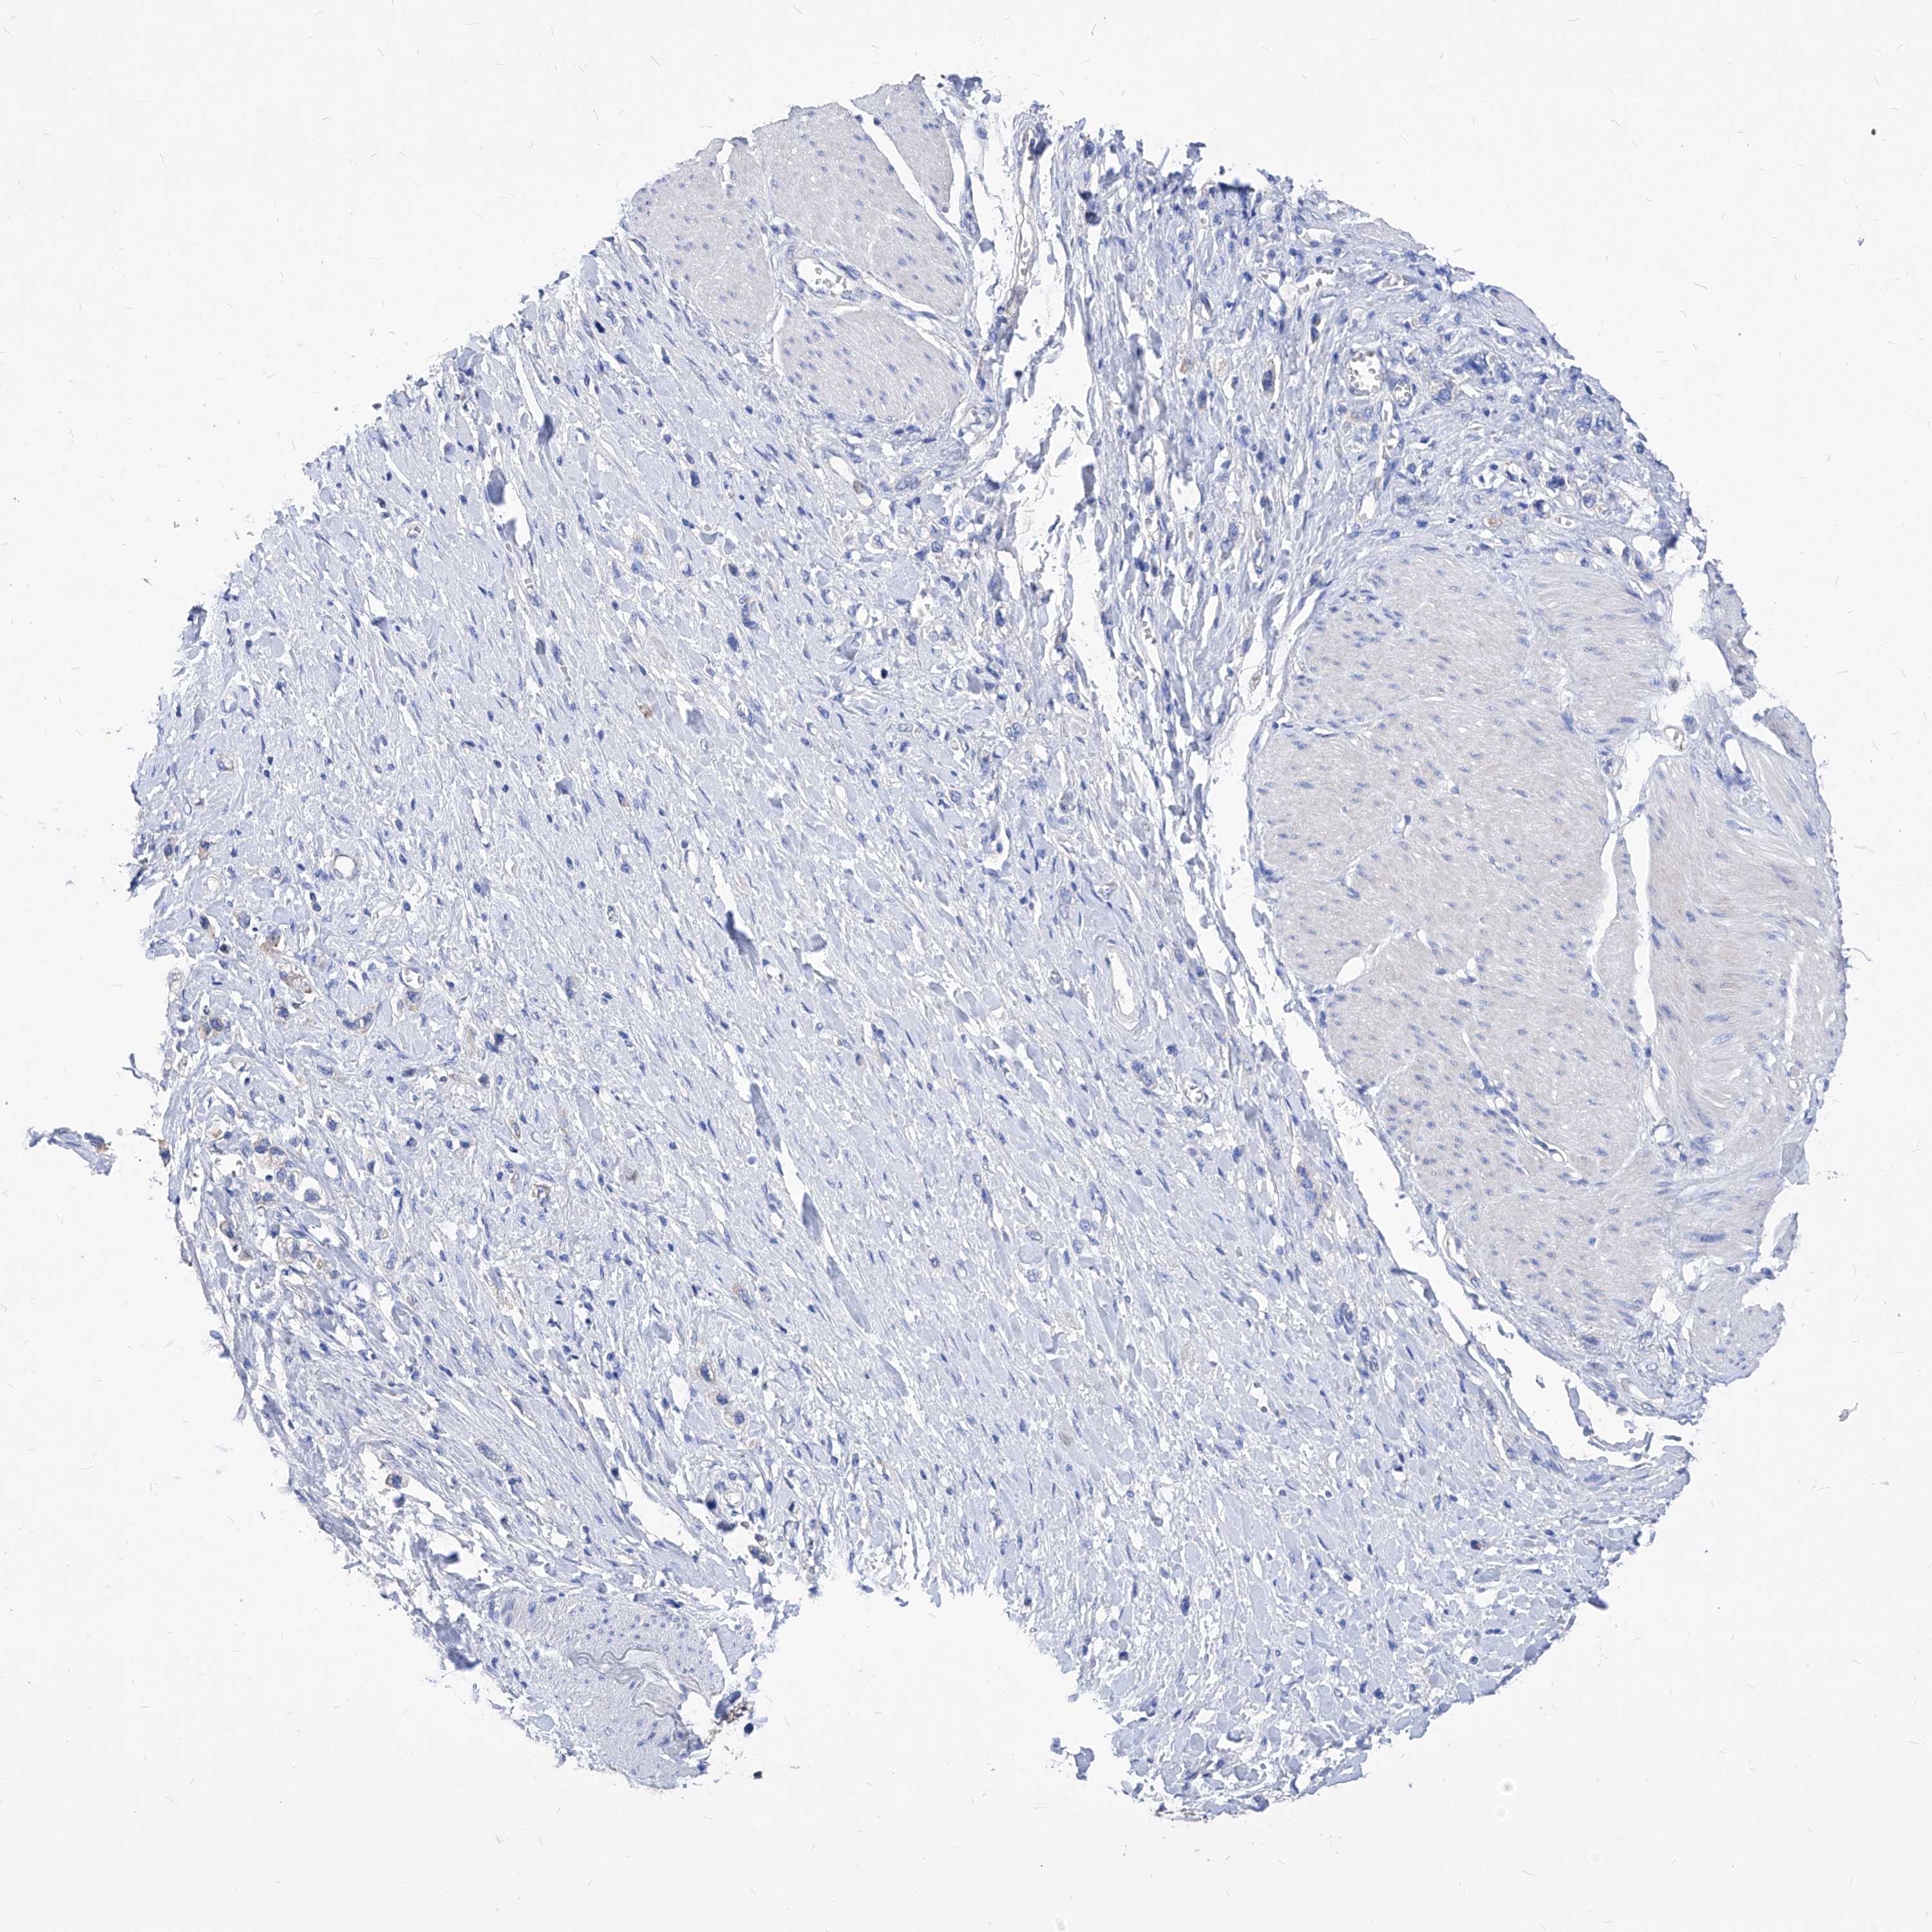

STOMACH CANCER - Protein expressioni

A mouse-over function shows sample information and annotation data. Click on an image to view it in a full screen mode. Samples can be filtered based on level of antibody staining by selecting one or several of the following categories: high, medium, low and not detected. The assay and annotation is described here.

Note that samples used for immunohistochemistry by the Human Protein Atlas do not correspond to samples in the TCGA dataset.

Antibody stainingi

Antibody staining in the annotated cell types in the current human tissue is reported as not detected, low, medium, or high, based on conventional immunohistochemistry profiling in selected tissues. This score is based on the combination of the staining intensity and fraction of stained cells.

Each image is clickable and will lead to virtual microscopy that enables deeper exploration of all samples and also displays staining intensity scores, fraction scores and subcellular localization as well as patient and tissue information for each sample.

HPA030419

HPA030420

HPA030422

CAB025196

CAB080286

CAB080287

Staining

High

Medium

Low

Not detected

Intensity

Strong

Moderate

Weak

Negative

Quantity

>75%

75%-25%

<25%

None

Location

Nuclear

Cytoplasmic/membranous

Cytoplasmic/membranous,nuclear

Adenocarcinoma, NOS

Adenocarcinoma, High grade